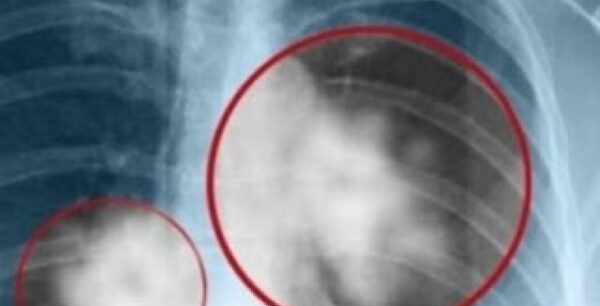

«Ακίνδυνες» καλοήθεις παθήσεις του μαστού μπορεί να εξελιχθούν σε καρκίνο

Μελέτη που έγινε από τους επιστήμονες της Mayo Clinic, σε 698 γυναίκες, διαπίστωσε ότι οι «ακίνδυνες» καλοήθεις παθήσεις του μαστού μπορούν, έπειτα από μερικά χρόνια να εξελιχθούν σε καρκίνο. Συγκεκριμένα, οι ερευνητές προσπάθησαν να βρουν σε τι ποσοστό οι γυναίκες με άτυπη υπερπλασία και των δύο τύπων, θα αναπτύξουν καρκίνο του μαστού σε 5, σε […]